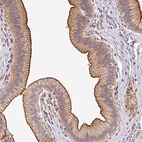

Immunohistochemical staining of human gall bladder shows distinct membranous positivity in glandular cells.